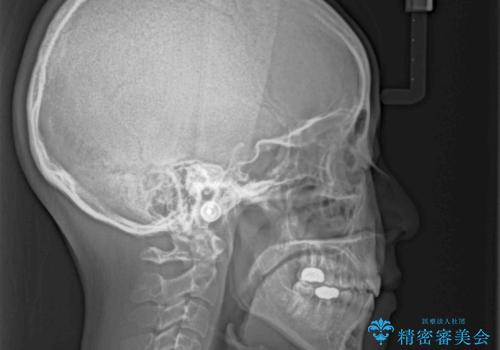

骨格的に下顎がやや前方にあるため、横顔のシルエットが著しく変化することはありませんでしたが、口元はスッキリと引っ込み、唇が閉じやすくなりました。